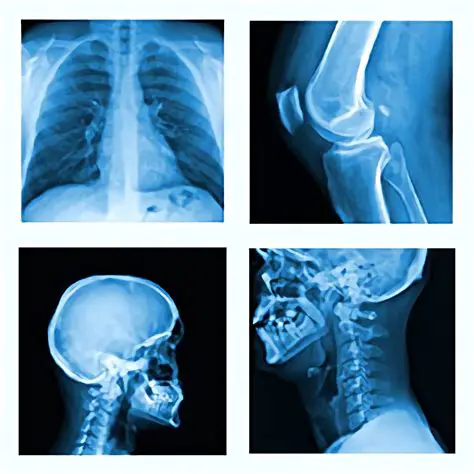

Optimize radiographic examination techniques